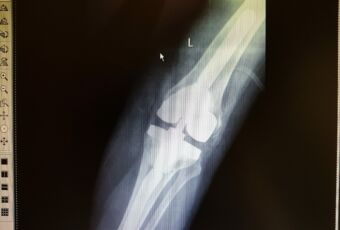

- Наименование операции: ревизионное эндопротезирование коленного сустава.

- Используемое оборудование, методика: использовался специальный установочный инструментарий для имплантации полусвязанного эндопротеза коленного сустава LCCK Zimmer, методика операции: удаление нестабильного компонента тотального эндопротеза коленного сустава, подготовка поверхностей костной ткани к имплантации ревизионного компонента, примерка компонентов эндопротеза, установка ревизионных связанных компонентов при помощи костного цемента. Операция – ревизионное эндопротезирование коленного сустава связанным эндопротезом.

- Краткая информация о пациенте, диагноз: Пациентка С., 1952 г.р. Диагноз: Асептическая нестабильность компонентов эндопротеза левого коленного сустава.

- Краткое описание хода операции (основные этапы): Иссечены рубцовые ткани по периферии сустава. Удален полиэтиленовый вкладыш и два винта с шайбами из бугристости большеберцовой кости. Затем с помощью долот и набойников удалены последовательно бедренный и большеберцовый компоненты. По направителям произведены минимальные опилы большеберцовой и бедренной костей. Затем развертками обработан канал большеберцовой кости до размера 14 мм, а бедренной кости до 17 мм. Имплантированы примерочные компоненты на интрамедуллярных ножках, отмечены дефекты, требующие заполнения металлическими блочками и стабильность сустава. После этого на 1 дозу костного цемента имплантированы бедренный компонент («Е») LCCK с ножкой 100/17 мм, большеберцовое плато 4 с ножкой оффсетной 100/14 мм, вкладыш LCCK 14 мм, 3 металлических блочка. Сустав вправлен, стабилен.

- Результат: имплантация ревизионного эндопротеза коленного сустава.